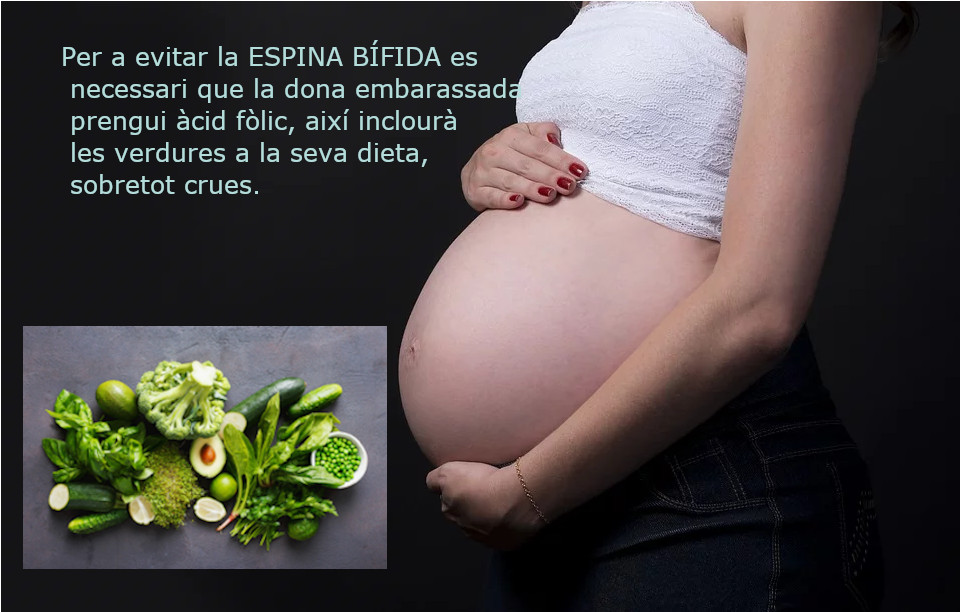

El pacient neurològic

Hi ha més de 600 malalties neurològiques, de molt diferent origen o causa. Es impossible fer referència a totes, pero de segur que hem sentit a parlar de: la Espina Bífida (malformació neurològica abans del naixement), malalties degeneratives com el Parkinson o Alzheimer o ELA, Meningitis (produïdes per microorganismes), Esclerosis Múltiple (autoimmue), derrames cerebrals que ocòrren per fragilitat dels vasos que irriguen el cervell, tumors cerebrals, i lesions medul.lars i cerebrals produïdes per accidents (la majoria accidents de tràfic).